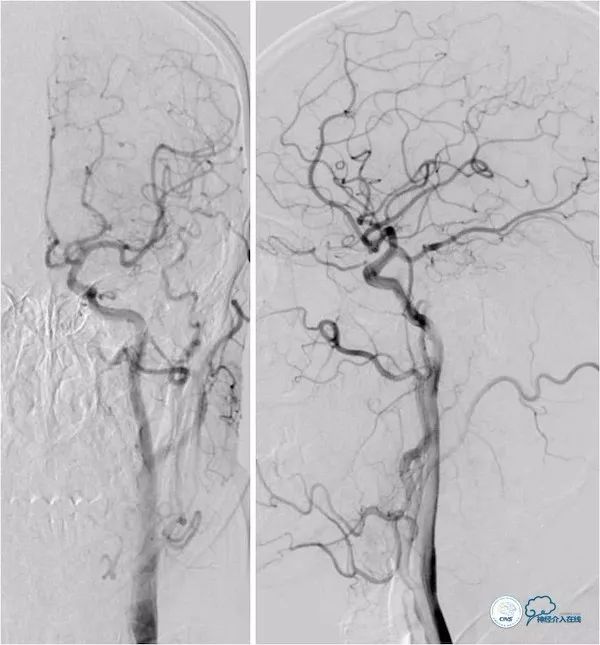

DSA:双侧颈动脉系统未见异常,双侧后交通动脉开放,右颈动脉造影可见基底动脉中上段显影。左椎动脉闭塞,右椎动脉V4段重度狭窄,基底动脉中段偏心重度狭窄(图5-8)。

图5

图6

图7

图8